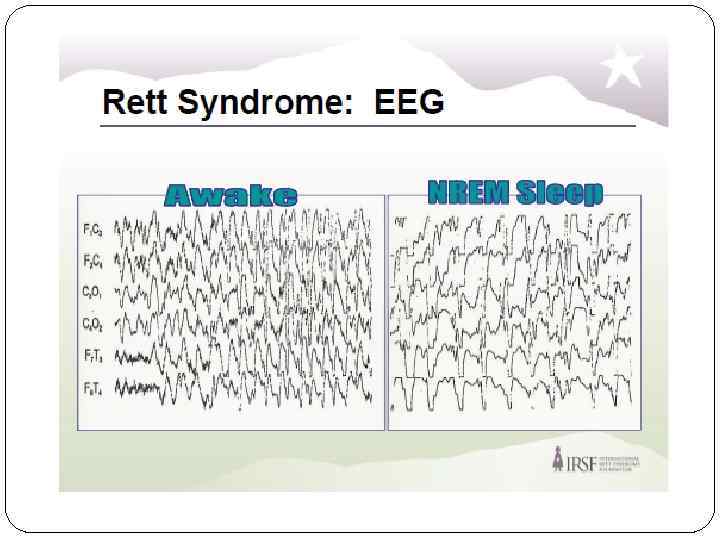

Данные ЭЭГ Практически во всех случаях, даже у тех пациентов, которые не имеют клинических судорог, наблюдаются аномалии на электроэнцефалограмме, начиная примерно с двухлетнего возраста. Сочетание замедления фонового ритма в период бодрствования и повышенной пароксизмальной активности во время сна существенно облегчает диагностирование синдрома Ретта и может считаться его дополнительным диагностическим критерием. В большинстве случаев наблюдается характерная эволюция изменений на ЭЭГ. Примерно с шестилетнего возраста доминирует монотонный а-ритм, который в дальнейшем, после 20 лет, имеет тенденцию локализации в центро-париетальной области.